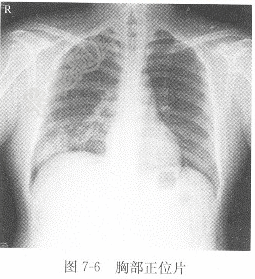

试题详情单项选择题男性,25岁,发热1周,X线影像见图7-6,X线诊断为( )。A、右下肺结核B、右下肺癌C、右侧胸腔积液D、右下肺炎正确答案:关注下方微信公众号,搜题查看答案热门试题男性,25岁,发热1周,X线影像见图7-脾外伤血清肌酐(Cr)测定题见图6-3。 动脉血氧饱和度(SaO2)房性期前收缩检查肾结石正常胸部正位片剩余碱(BE)血清甘油三酯(TG)阵发性室上性心动过速检查题见图6-2。 女性,68岁,胸痛1月,X线影像见图7-血常规女性,30岁,心悸、头晕2年,X线图像见肢体骨折正、侧位片血清碱性磷酸酶(ALP)尿常规男性,40岁,咳嗽1周,X线胸片见图7-肠结核